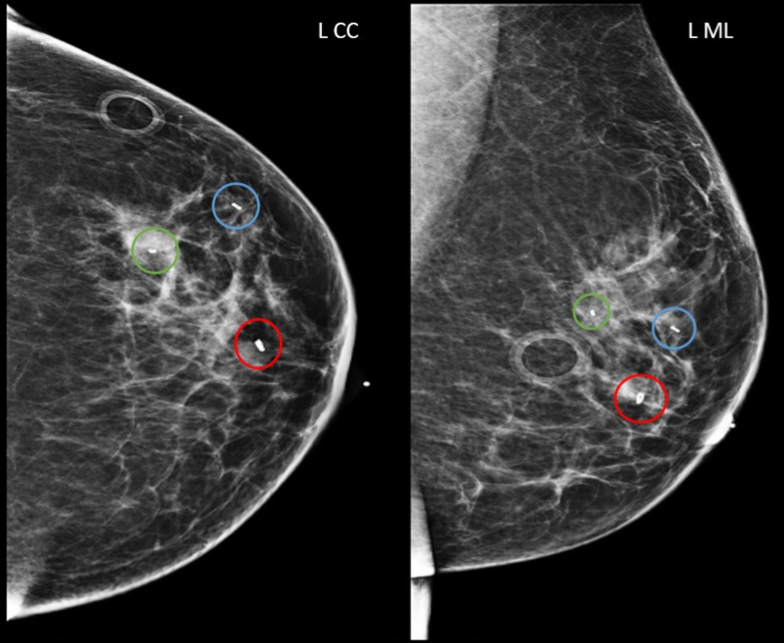

Post-procedure ultrasound is used to confirm the position of the marker relative to the targeted lesion (if placed under ultrasound guidance). Two-view mammography (craniocaudal and mediolateral oblique) is often performed to document final placement.

On ultrasound, the marker appears as a small echogenic focus with posterior shadowing or reverberation artefacts, depending on the material used. On mammograms, the marker appears as a small, metallic, high-density object on a mammogram, visible as a white or bright spot.

Subareolar 12 o’clock region biopsied mass with ring-shaped biopsy marker (red circles).

1 o’clock 5 cm from nipple biopsied mass with barbell-shaped biopsy marker (blue circles).

1 o’clock 6 cm from nipple biopsied calcifications with bar-shaped biopsy marker (green circles).

Craniocaudal (left image) and mediolateral (right image) views. L CC, left craniocaudal; L ML, left mediolateral